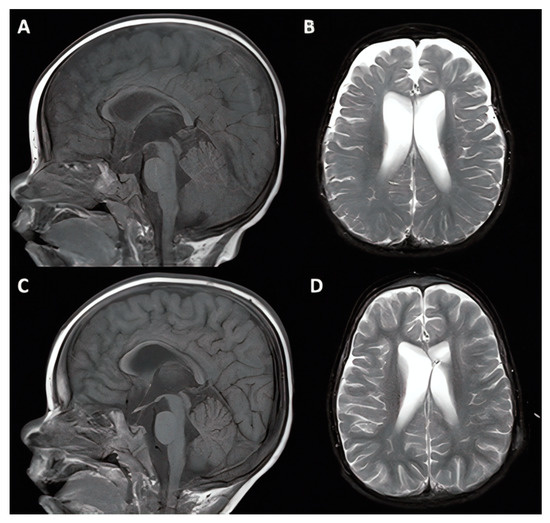

3.1.4. Cases #7–8. Hydrocephalus with Hunter Syndrome

| 7 | 12 y, M |

|

| 8 | 10 y, M |